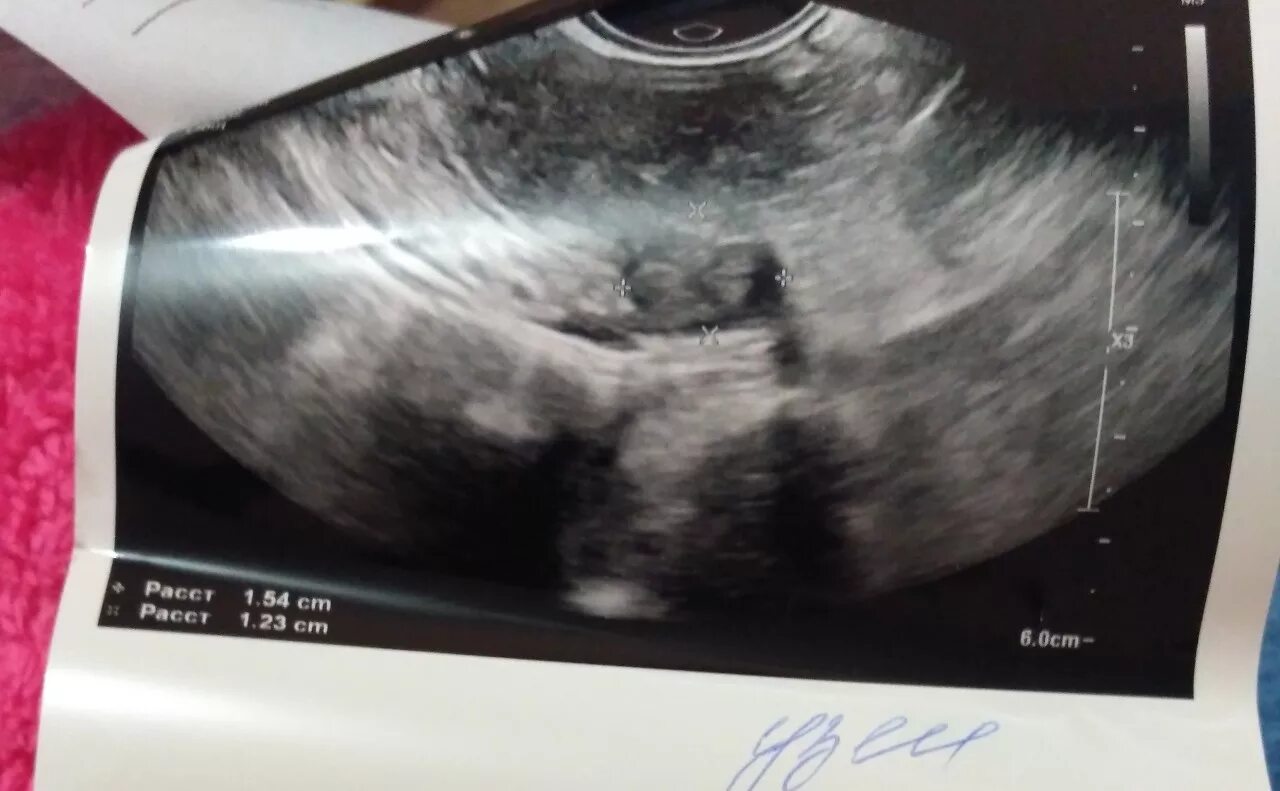

Цервикоз шейки матки